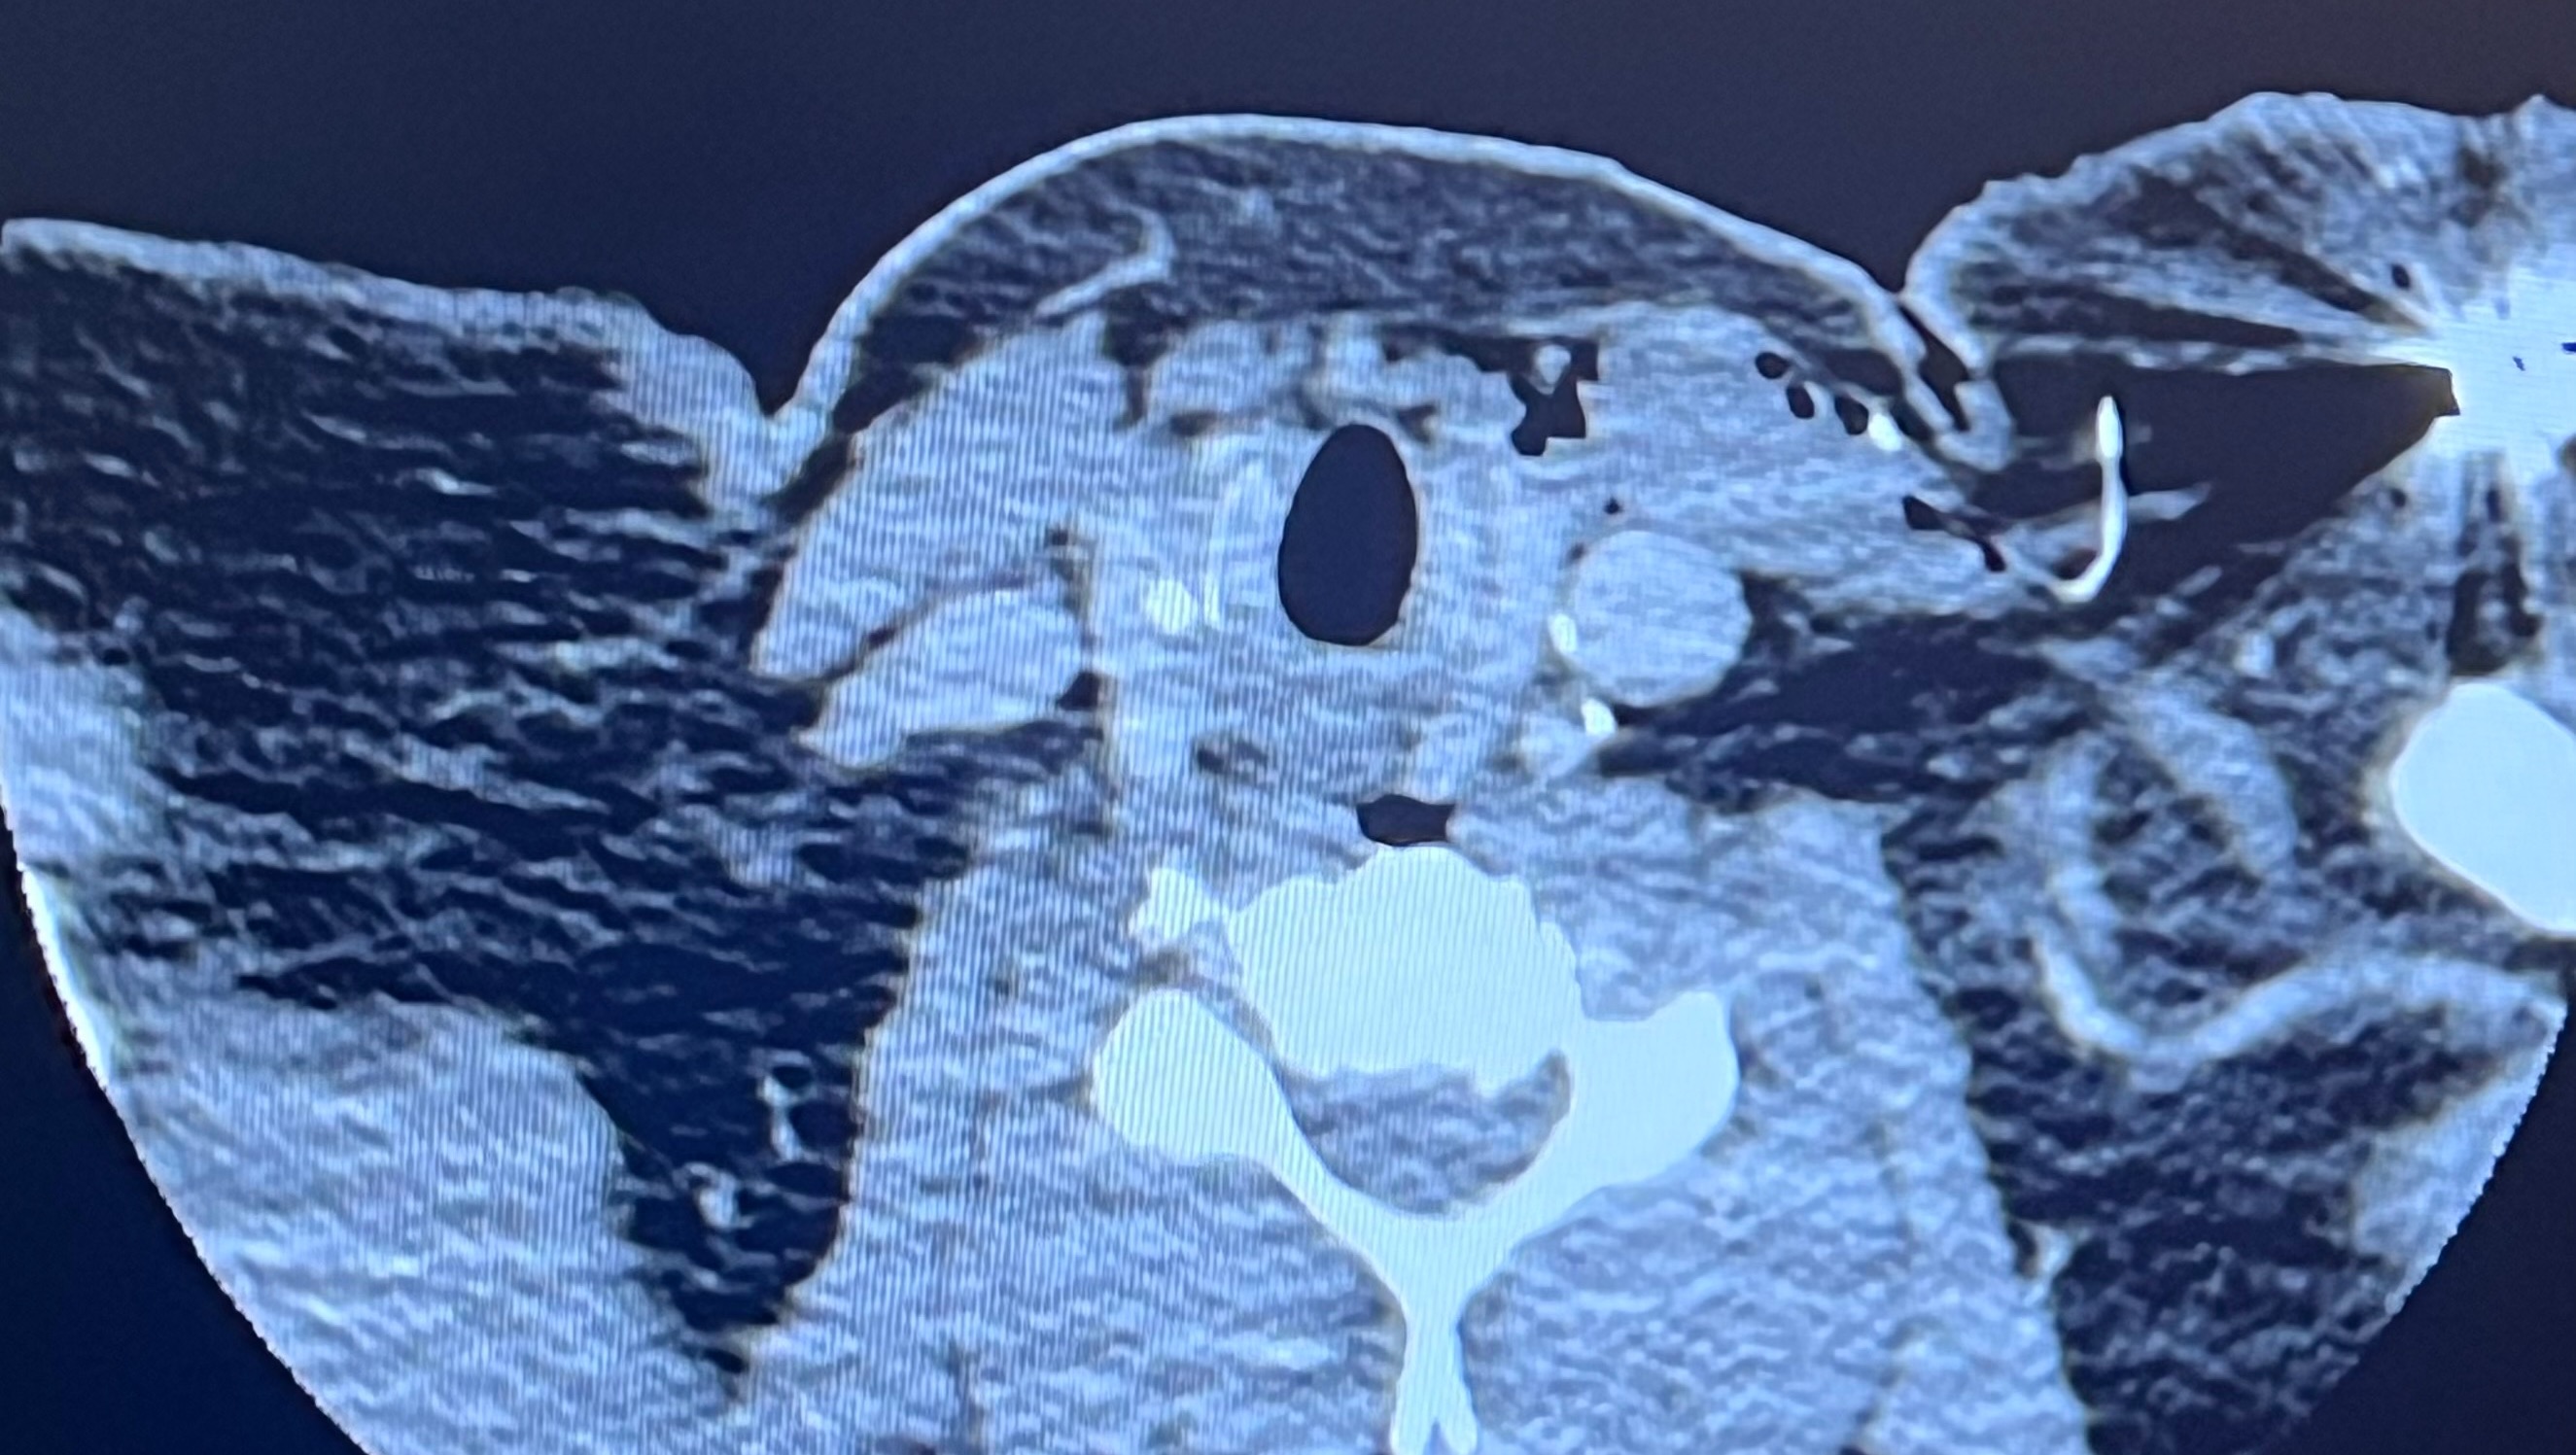

Over the last 10 + years Rori has developed Myoclonic and Tonic clonic seizures. They have rapidly increased and affect all of her daily life. Her last 43 hour brain scan (EEG) showed over 150 seizures. Over the last 2 years the seizures and the medication side effects got so bad she had to stop her business. Some days she has problems forming basic sentences, cooking, and even basic chores. Nathan is trying as hard as he can to continue to support their family while driving Rori to all the doctors appointments from eastern Washington to UW medical in western Washington for doctors, all shopping pretty much everything that needs to be done. This coming week, Rori will be going in for a surgery that is like a pace maker for her brain that will send a pulse through her brain to help send shock waves to hopefully help her have less seizures. Between this and the 4 medications she takes, she hopes to regain somewhat of a normal life for a bit. After surgery, every 1.5 to 2 weeks Nathan will need to take the day off, take Rori to the doctor to have the device calibrated for the next 6 plus months. Between this and missing work, and the 200 miles round trip it’s going to add up. The surgery bill, the hospital stay, the hotel stay for Nathan, and much more is all beginning to add up and weighing on Nathan’s shoulders as he tries to care for his wife.